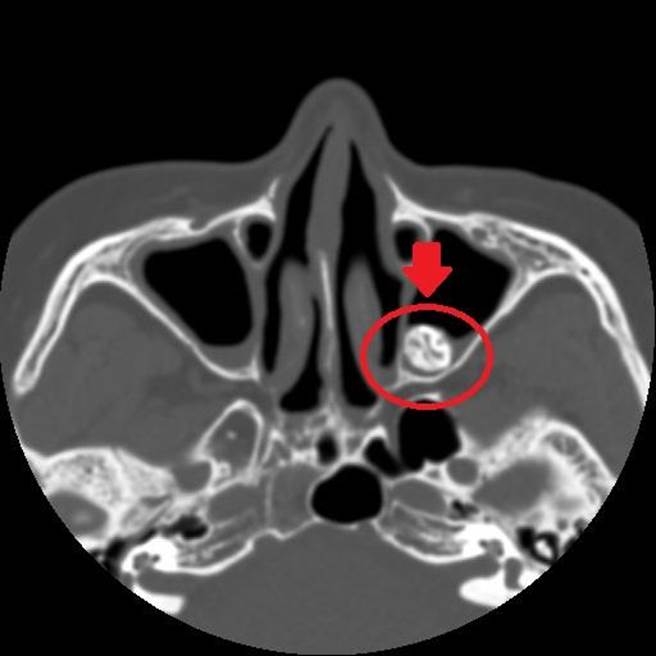

經核磁共振檢查,在婦人的左上顎竇位置處,發現1顆外型及密度都疑似「牙齒」的不明物體,研判是「異生齒」作祟,醫師建議藉由外科手術取出,徹底改善病灶;婦人術後隔天即出院返家,日前回診頻頻感謝醫師,大讚「不鼻塞也不頭痛了」。

田輝勣指出,這顆鼻竇異生齒位置十分特別,若採傳統手術方式,不僅傷口大,且術後癒合時間長,經溝通後,患者同意採用「自然孔」(鼻腔)執行手術,過程中透過磁導航3D立體定位系統,快速找到異生齒位置並取出,前後僅耗時30分鐘,取出之異生齒約2公分大。